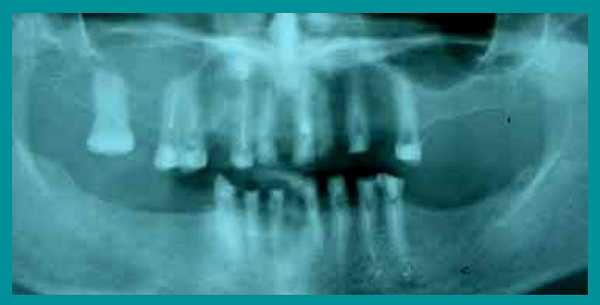

Трудности с пережевыванием пищи, отсутствие зубов, недовольство своим внешним видом, невозможностью улыбаться окружающим - вот неполный перечень тех жалоб, с которыми пациентка обратилась за стоматологической помощью. Из опроса выяснилось, что из-за страха перед лечением визит к стоматологу откладывался надолго, а точнее - на 31 год…

Осмотр выявил очень сильную горизонтальную стираемость верхних и нижних зубов, снижение высоты прикуса и изменение его из нормального в обратный (нижние зубы при смыкании находились впереди верхних). Одновременно на ортопантомограмме височно-нижнечелюстного сустава определялся двухсторонний подвывих нижней челюсти.

После осмотра и рентгенологического обследования зубочелюстной системы был предложен следующий план лечения: